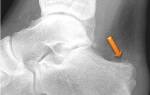

- рентген;